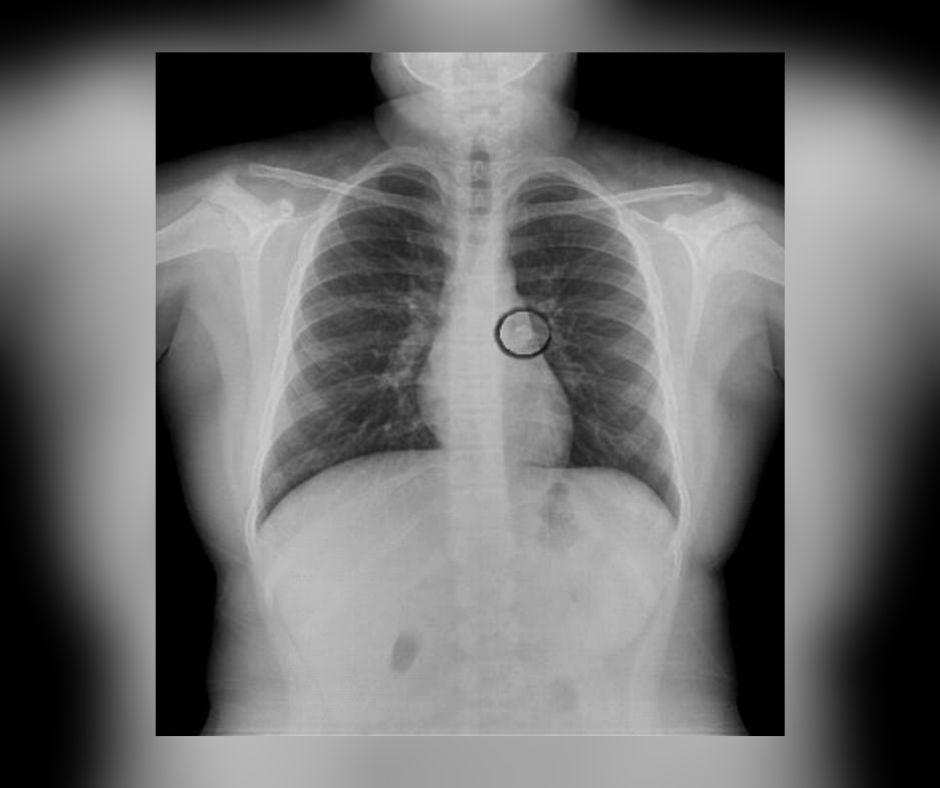

Dopiero następnego dnia, kiedy dziewczynka cały czas się skarżyła na ból w nodze, mama postanowiła zabrać ją do lekarza, by sprawdzić, czy podczas nieszczęśliwego upadku nie doszło do kontuzji. Niestety po wykonaniu prześwietlenia okazało się, że dziewczynka ma złamaną kość piszczelową i strzałkową.

Zdjęcie RTG dwulatki

Zdjęcie RTG dwulatki © TikTok